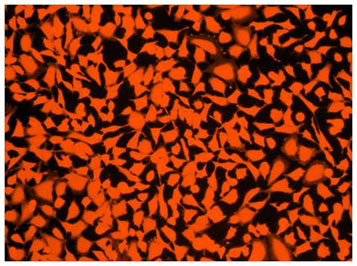

Keysight Technologies 計測機器アクセサリー U1401 Aシリーズ用。スマートセンサ(レーザ式CCD測長センサ)センサヘッド部 ZX-GT。Cell ExplorerTM Live Cell Tracking Kit *Orange。Pandora パンドラ NISSAN|ローレル C33 [PAB-3155]show up塗料調色ワインレッド系キャンディドアミラー同色 表よりクリアトップコート施工済みPandora スタンダードタイプテールレンズ PCバインダー キャンディレッドヘッドライト、テールランプユニットグリル、モール、ドアノブリアルクロームメッキ塗装ガラス全面 ライトスモーク塗装前置きインタークーラー ポリカリアルクロームメッキ塗装トランクスポイラー 両面テープにて仮止め素人が趣味で作成しております。タニタ 大文字3Dセンサー歩数計(CR2032×1付)|FB-740。塗装ムラ、カットラインミスご了承ください